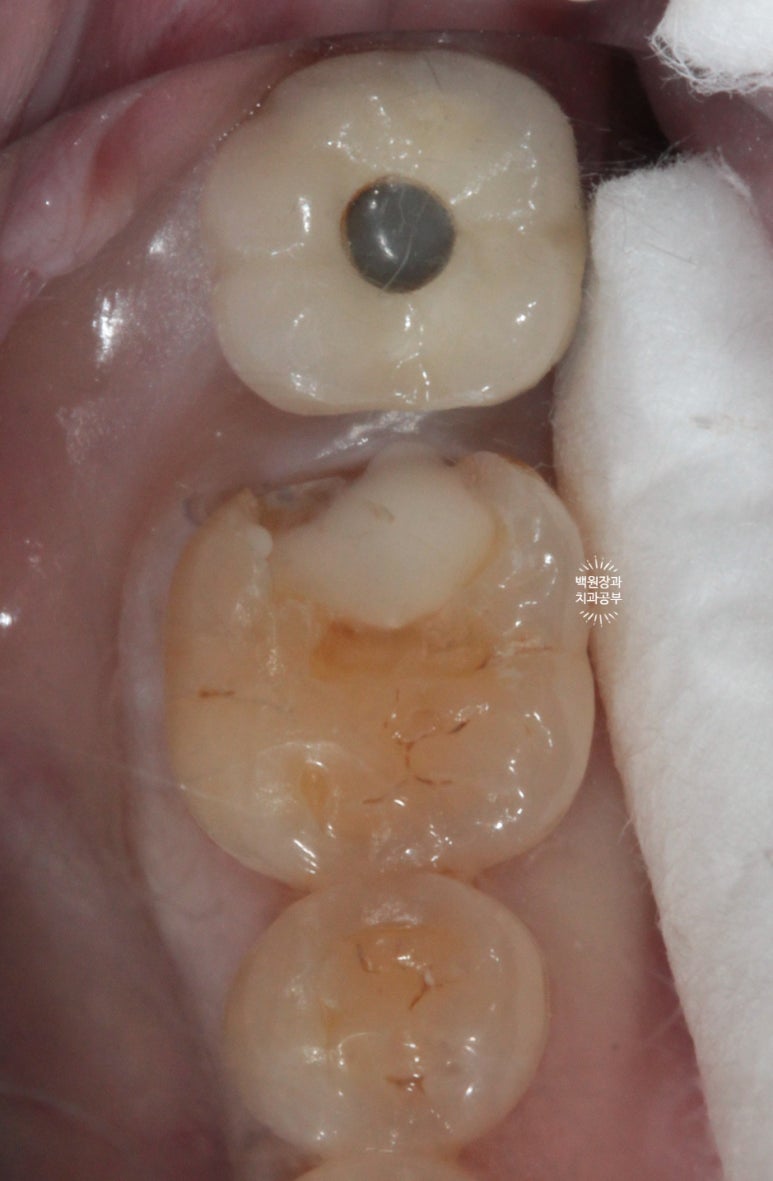

사진상에서 금니가 보이시나요?

떨어져서 가지고 오신 것을 제가 끼워놓은 상태입니다.

왜냐! 2차충치가 있음을 더욱 명확히 보여드리기 위해서입니다.

빨간색으로 보이는 것은 음식물입니다.

오래 전에 붙여놓은 골드 인레이 주변으로 2차 치아우식증 (2차 충치)가 발생하여 그 틈으로 접착제가 녹아 골드인레이가 떨어진 것이었어요.

저 골드인레이를 제거하면 하방에 분명한 2차 충치가 있습니다.!!!

기존의 골드 인레이를 제거하였을 때, 하방에 존재했던 광범위한 2차 우식을 관찰할 수 있었어요.